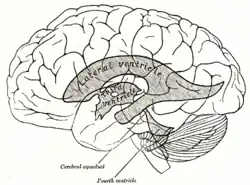

Корональный срез через передние рога боковых желудочков- Боковой срез человеческого мозга

Проекция желудочков головного мозга на его поверхность

Проекция желудочков головного мозга на его поверхность